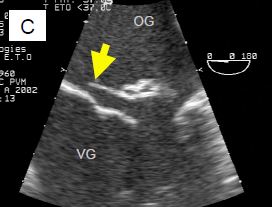

L'échocardiographie démontre que la maladie dégénérative peut prendre plusieurs aspects (Figure 11.64).

Figure 11.64 : Images ETO d’insuffisance mitrale sur dégénérescence myxoïde. A : excès de tissu avec ballonnisation, épaissisement localisé et prolapsus des deux feuillets ; la flèche indique le déplacement de l’extrémité des feuillets en arrière du plan de l’anneau mitral (trait pointillé). B : prolapsus isolé de P2. C : prolapsus de P2 avec rupture de cordage (indiqué par la flèche). D : rupture complète de muscle papillaire avec fragment de pilier attaché à l’extrémité du feuillet antérieur.